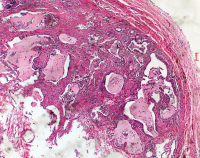

Respiratorische Bronchiolitis

Abbildung 1: Mikroskopisches Erscheinungsbild von RB mit pigmentierten Makrophagen, die eine respiratorische Bronchiole ausfüllen und in die umgebenden Lufträume austreten. Hämatoxylin- und Eosin-Färbung, Vergrößerung x 48.

Keywords: Histologisches PräparatRespiratorische Bronchiolitis